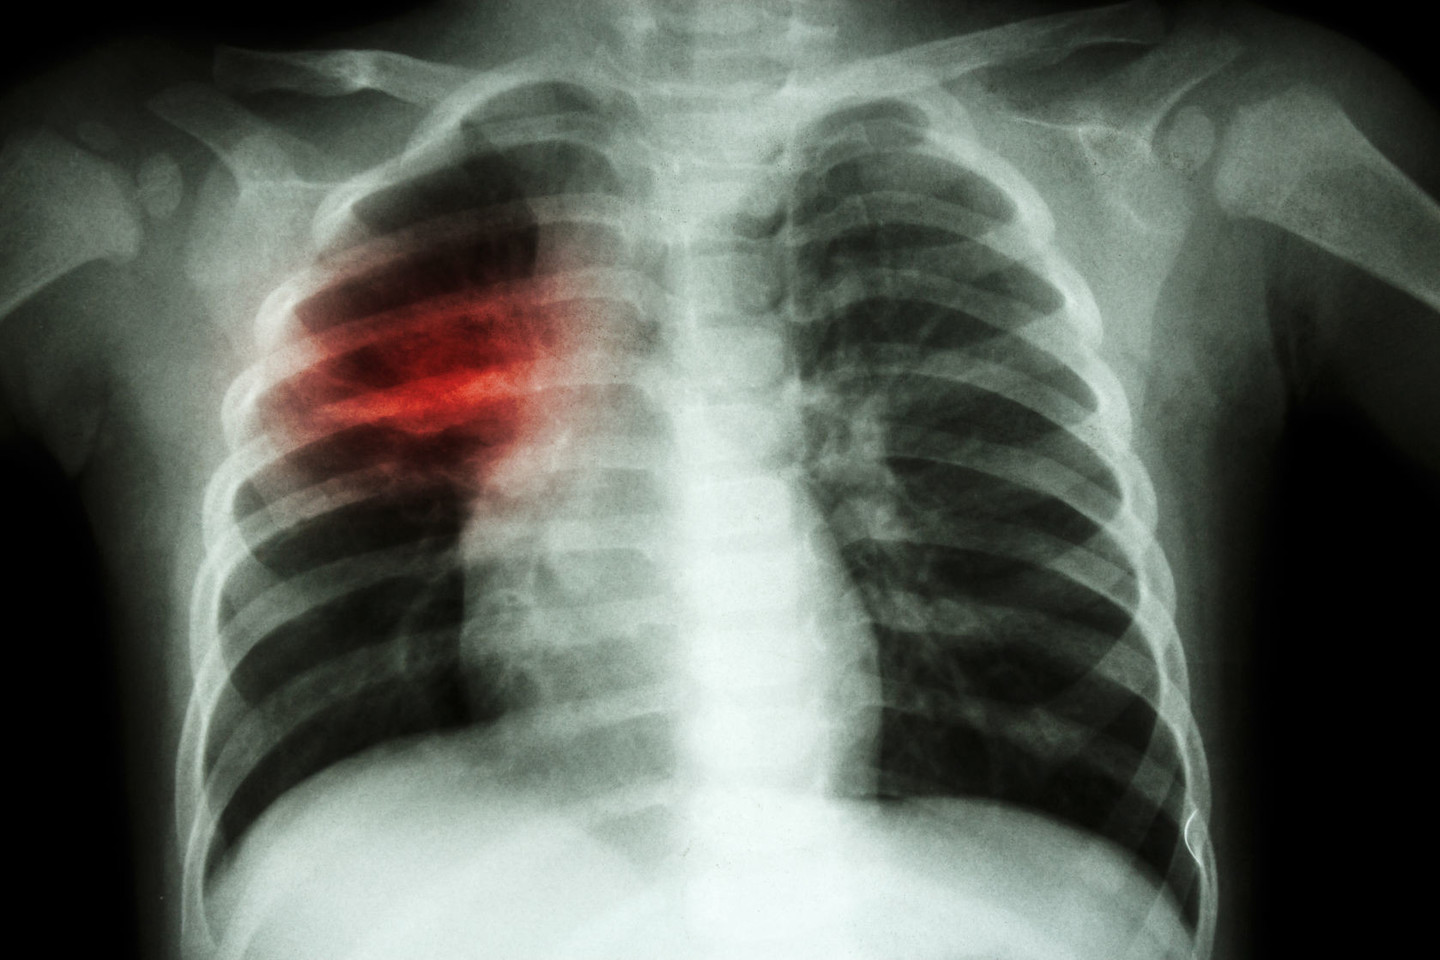

Vaikų tuberkuliozės atvejai rimtėja

Tuberkuliozė – tema, kuri, deja, nepraranda aktualumo. Kauno klinikinės ligoninės gydytoja Dalia Steponavičienė pristatė klinikinius atvejus, kada vaikų tuberkuliozės požymiai būna pasislėpę po kita kaukę – susiję su kitomis ligomis.

„Lyginant su ankstesniais metais, vaikų sergamumas tuberkulioze šiek tiek padidėjo: 100-tui tūkstančių gyventojų tenka 13,6 atvejo. Skaičius nesiekia 20 atvejų, tad tai nėra labai daug. Vis tik stipriai neramina tai, kad vaikai serga labai rimtomis tuberkuliozės formomis – ir atvira, ir netgi atsparia vaistams. Tiek daug paauglių, sergančių atvira tuberkuliozės forma, dar neturėjome, o aš su tokiais ligoniais dirbu jau labai seniai“, – iškalbingai pabrėžė D. Steponavičienė.

Pasak gydytojos, vaikų tuberkuliozė – kaip lakmuso popierėlis ar rodiklis, kad visuomenėje turime nemažai atviros tuberkuliozės atvejų tarp suaugusiųjų. Jie nesigydo ir platina ligą. Maždaug apie 30 proc. suaugusiųjų, kurių tuberkuliozės atvejai naujai nustatyti, nutraukia gydymą ir vaikšto tarp mūsų galėdami užkrėsti kiekvieną. Susirgus tuberkulioze svarbiausia iki galo išsigydyti.